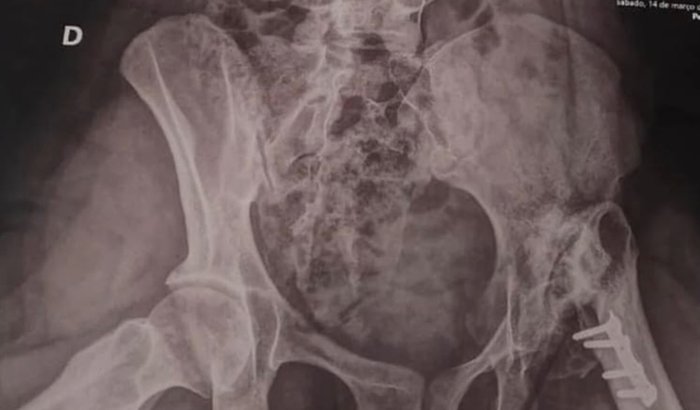

Sou mãe da Grazielle minha filha precisa de uma cirurgia

ONGs ela já está na fila de espera do sus a mais de 5 anos

Então a gente decidiu ir pro particular por que o caso dela

É sério por isso estou aqui pedido a ajuda das pessoas

Essa cirurgia está estimada no valor de 70.000